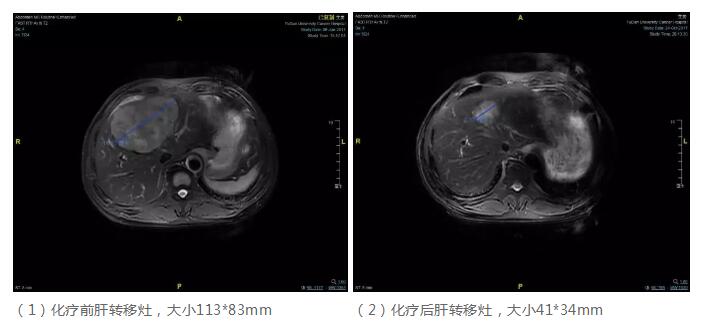

腹部MR:肝左叶较大占位,约113*83mm;

患者盆腔CT可见乙状结肠壁略增厚,乙状结肠肿瘤原发灶未见明显外侵表现,两侧髂血管旁多发小淋巴结;腹部MR可见肝脏左叶占位,大小约113*83mm,T1WI低信号,T2WI混杂高信号,增强后不均匀强化,边界不清,肝内血管正常,肝内胆管未见扩张,胆囊、胰腺及脾脏未见异常,腹膜后未见肿大淋巴结;外院PET/CT提示乙状结肠肿瘤,肝转移。目前胸部CT未见明显转移征象。综上,影像学特点符合乙状结肠癌伴同时性肝转移。

患者目前诊断明确,乙状结肠癌伴同时性肝转移,目前肝左叶较大占位,约113*83mm,CEA水平升高,RAS野生型。肝转移灶单一巨大,为潜在可切除病例,CRS评分2分,但转移病灶较大,不排除有合并小的卫星病灶可能,建议行术前新辅助化疗,评估肝转移灶治疗后退缩情况,以期达到满意的R0切除,并尽可能的保留足够的肝脏功能,达到生存获益。

后续治疗

根据多学科讨论结果及建议,患者于2017.06-2017.10行FOLFIRI+爱必妥方案化疗6程,2017.10月行腹部MR评估肝转移灶提示:肝脏转移瘤较前明显缩小,大小41*34mm,CEA:80,化疗后评估肝转移灶退缩显著,可考虑手术切除。